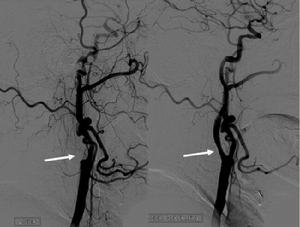

1.缺血性腦血管病:腦動脈狹窄(圖2),急性或慢性腦動脈閉塞(圖3),顱內靜脈竇血栓等。

神經介入技術(圖2 頸動脈嚴重狹窄支架治療)

神經介入技術(圖3 頸動脈閉塞再通支架管腔成形)